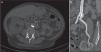

Se solicitó un angio-TC que demostró una gran lesión calcificada intraluminal (coral reef) que condicionaba una lesión preoclusiva a nivel de la arteria ilíaca común izquierda, inmediatamente tras la bifurcación aorto-ilíaca. Tanto la arteria del injerto como la anastomosis y la arteria hipogástrica receptora estaban permeables (fig. 1).

Se optó por un tratamiento endovascular mediante punción femoral bilateral eco-guiada con anestesia local. Se implantó stent bilateral recubierto balón-expandible Advanta® V12 8×38mm (Atrium, Hudson, NH, EE.UU.) en la bifurcación aorto-ilíaca sin presencia de estenosis residual en la arteriografía de control postimplante (fig. 2). Se utilizó esta disposición en kissing para cubrir toda la lesión evitando comprometer el ostium del eje ilíaco contralateral.